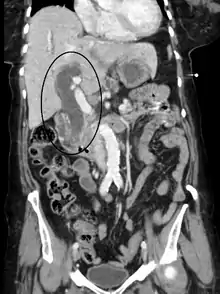

Imaging

Medical imaging such as ultrasound, CT scan, and HIDA scans are useful for detecting bile duct blockage.[32]